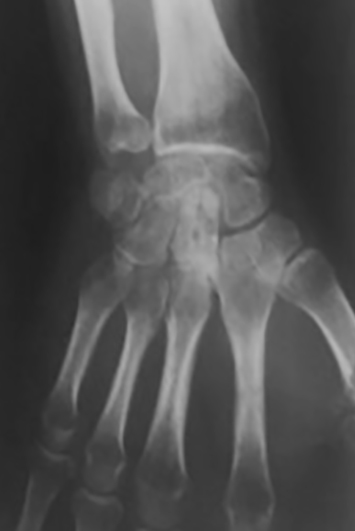

Se extrajeron los alambres y el fijador externo a las 6 semanas. El paciente empezó con ejercicios activos y pasivos de recuperación del rango de movimiento de mano y puño. A los 12 meses el paciente no mostraba dolor, a pesar de que ya se visualizaban cambios radiográficos con osteocondensación del hueso grande, pero sin colapso carpiano (Figura 4).

En cuanto a la movilidad a los 6 años, encontramos una mayor pérdida de la flexión del puño, comparada con la extensión. Pensamos que esto se deba a la pérdida del componente de flexión de que se observa entre la primera y segunda fila del carpo normalmente y que corresponde aproximadamente a 35° de flexión de puño (7). Por último, no encontramos clínica de dolor espontáneo y tampoco relacionada con la práctica de deporte de contacto, a pesar de la osteocondensación radiográfica evidente al año y que muestra cambios radiológicos significativos con un colapso capito-semilunar a los 6 años de seguimiento (Figura 5). Esto guarda relación con las limitaciones observadas clínicamente.